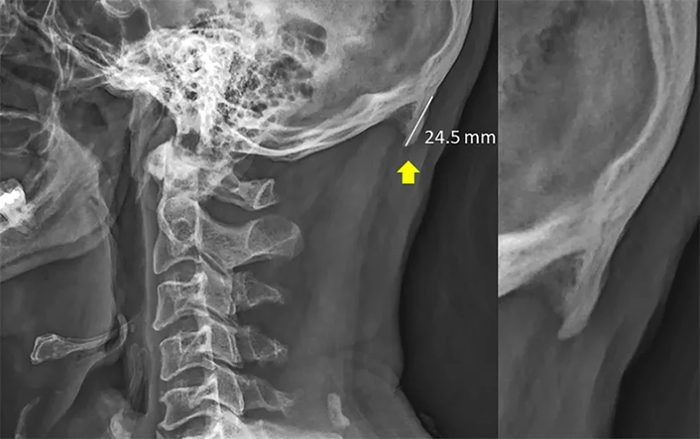

Hình ảnh được trích ra từ báo cáo đang khiến nhiều người bất ngờ.

Nhóm nghiên cứu theo đó cho biết người dùng thiết bị di động thường xuyên thường nghiêng đầu về phía trước để nhìn màn hình. Động tác này làm thay đổi trọng lượng của đầu từ phần cột sống đến các cơ phía say đầu khiến một phần xương phát triển thêm ở gân và dây chẳng. Phần xương này có cấu trúc như sừng và mọc ra từ đáy của hộp sọ.

“Phát hiện của chúng tôi làm dấy lên quan ngại về sức khoẻ hệ cơ xương khớp của người trẻ và nhấn mạnh nhu cầu can thiếp vào xu hướng này thông qua giáo dục cải thiện tư thế,” nhóm nghiên cứu nói trong báo cáo của mình. Được biết, để đưa ra được kết quả này, nhóm nghiên cứu đã xem xét 1.200 hình ảnh chụp X-ray tại Queensland với người tham gia khảo sát thuộc nhiều độ tuổi khác nhau.